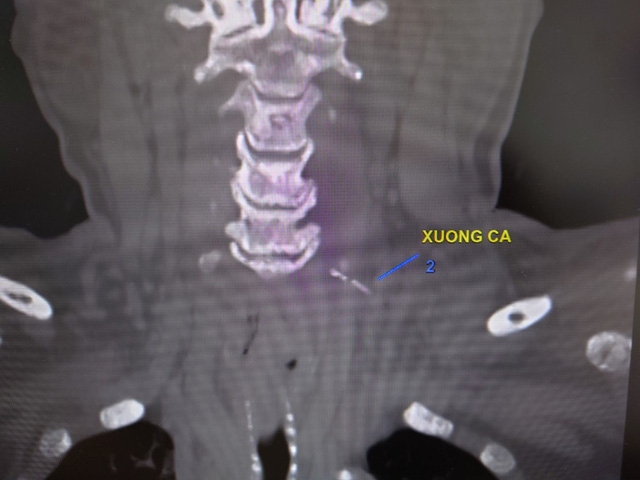

Ông Phạm Thanh Phong, Phó giám đốc Bệnh viện Đa khoa Trung ương Cần Thơ cho biết các bác sĩ khoa Ngoại Lồng ngực - Mạch máu vừa phẫu thuật cứu sống bệnh nhân bị áp-xe cổ lan xuống trung thất nghiêm trọng do hóc xương cá.Nữ bệnh nhân T.T.H. (64 tuổi, ngụ huyện Cái Bè, Tiền Giang) nhập viện chiều 19/1 trong tình trạng đau nhiều vùng cổ. Ba ngày trước đó, bà H. ăn cá dứa nuốt phải xương. Sau khi có cảm giác vướng ở vùng họng, bệnh nhân cố nuốt cơm rồi móc họng 4-5 lần. Tuy nhiên, xương cá không "trôi" mà cổ ngày càng đau, sưng to nên vào Bệnh viện Đa khoa Trung ương Cần Thơ điều trị.Kết quả chụp cắt lớp vi tính cột sống cổ có tiêm thuốc cản quang cho thấy bà H. bị áp-xe cổ lan trung thất do dị vật. Sau khi có chỉ định mổ cấp cứu, các bác sĩ khoa Ngoại Lồng ngực - Mạch máu và khoa Phẫu thuật - Gây mê hồi sức đã bóc tách vào ổ áp-xe dọc động mạch cảnh - thực quản và khí quản. Tại đây, kíp phẫu thuật thấy có nhiều mủ nên lấy làm kháng sinh đồ.